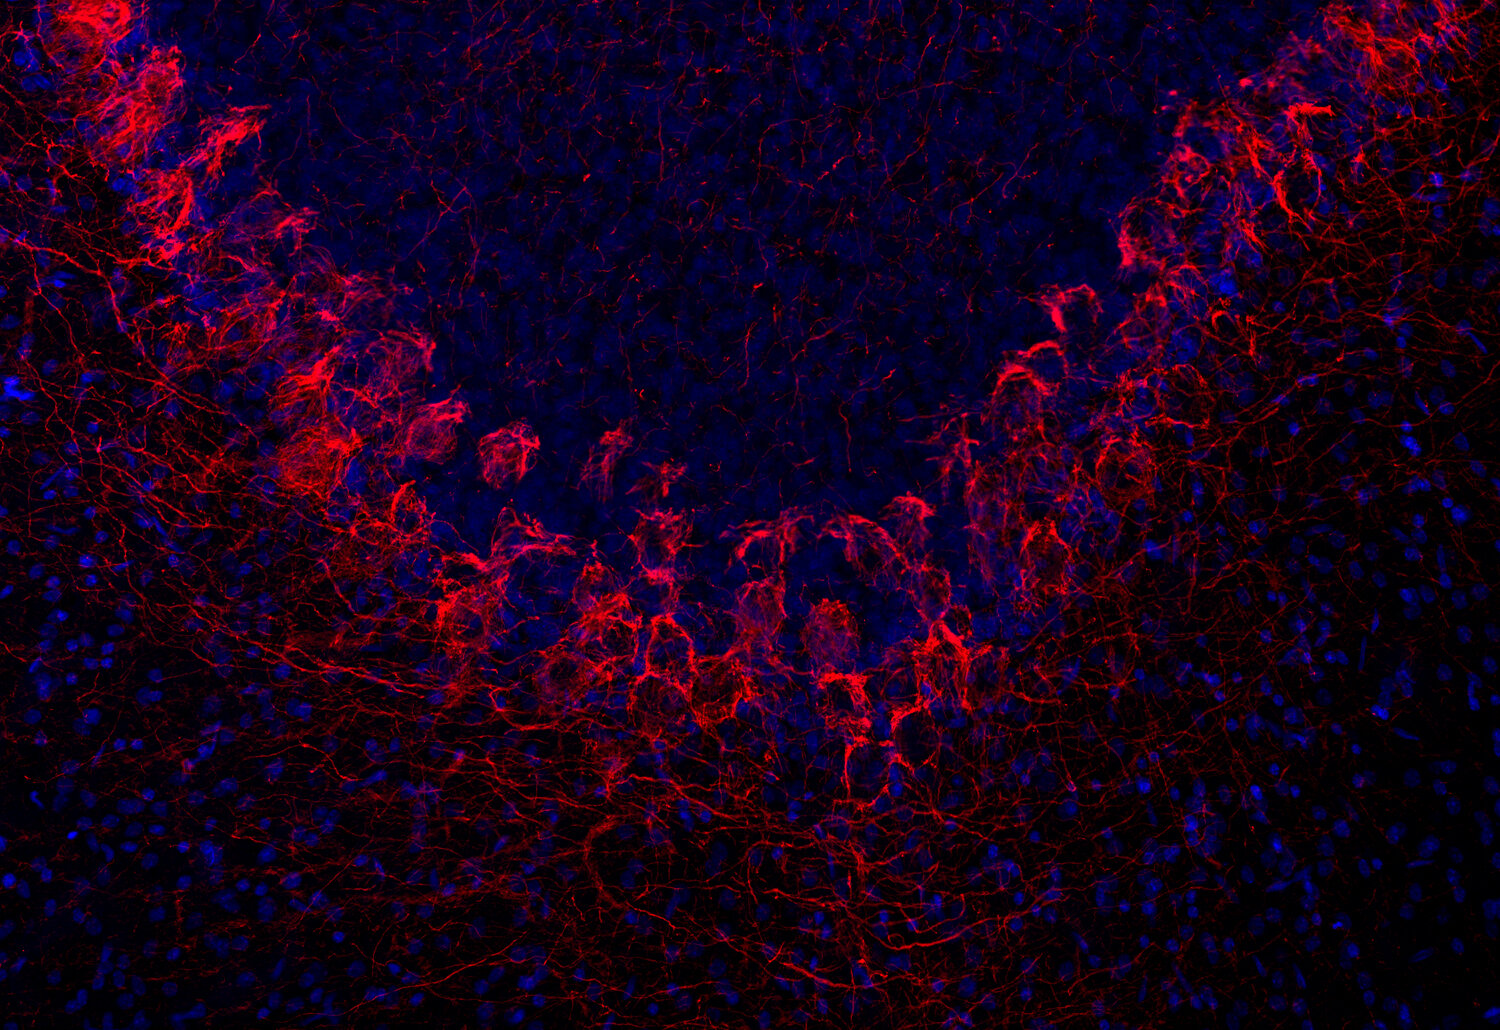

ICC: 1 : 500 up to 1 : 1000 gallery

IHC: 1 : 500 up to 1 : 1000 gallery

IHC-Fr: 1 : 500 gallery

Immunocytochemistry (ICC) on 4% PFA fixed cells. Immunoreactivity is usually revealed by fluorescence. Some antibodies require special fixation methods. For details, please refer to the “Remarks” section.

Immunohistochemistry (IHC) on 4% PFA perfusion fixed tissue with 24h PFA post fixation. Immunoreactivity is usually revealed by fluorescence or a chromogenic substrate. Some antibodies require special fixation methods or antigen retrieval steps. For details, please refer to the ”Remarks” section.

Neurofilaments (NFs) are intermediate filaments essential for providing structural support to neurons, particularly within axons. They play a crucial role in maintaining axonal diameter, which directly influences nerve conduction velocity (1). Neurofilaments are composed of three primary subunits - NF-L (light), NF-M (medium) and NF-H (heavy) – along with an NF-associated protein. In the adult central nervous system (CNS), α-internexin serves as the fourth neurofilament subunit, whereas in the peripheral nervous system (PNS), peripherin takes on this role (2).

Beyond their structural function, neurofilaments are also valuable biomarkers in both research and clinical settings. They are widely used in immunohistochemistry to stain and visualize axons, particularly in peripheral nerves and the CNS. Increased levels of neurofilament proteins in cerebrospinal fluid (CSF) or blood are strongly associated with neurodegenerative diseases, such as amyotrophic lateral sclerosis (ALS), multiple sclerosis (MS), and Alzheimer’s disease (3). In peripheral nerve studies, neurofilament staining is often combined with other markers, such as S100, to provide a more comprehensive assessment of nerve structure and pathology (4).